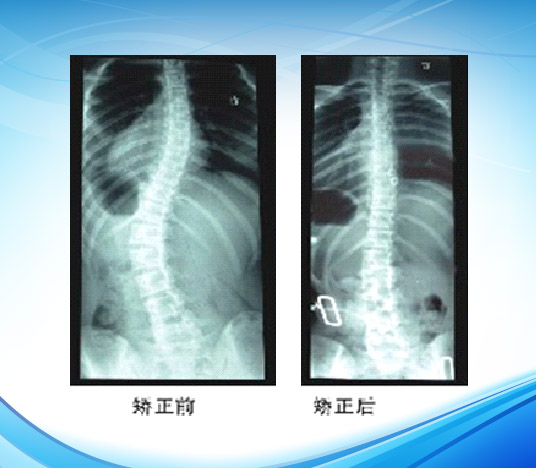

矫正结果的检验

检查矫形器的矫正结果不仅通过比较装配前后(装配后是指适应性练习完成两个星期之后) X线片侧弯角度进行检查,还要检查以下各点细节:

2 在完成适应性穿戴过程2周后,拍摄X线片(对X线片拍摄的要求是穿戴矫形器的站立位全脊柱正、侧位片)